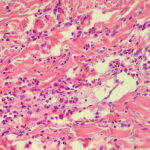

Eosinophilic annular erythema = حمامى حلقية بالحمضات